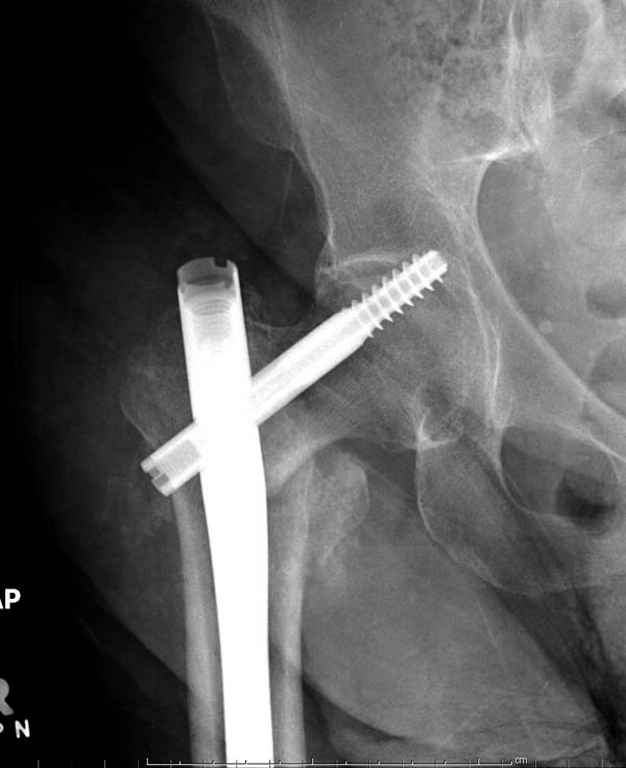

Перелом тут больше подвертельный. Нагрузка без торцевого упора на уровне перелома привела к телескопированию отломков на стержне. Ну и варус небольшой тоже свою лепту внес - если бы его не было, контактирующие латеральные стенки обоих отломков предотвратили бы укорочение, да и срослось бы за пару месяцев. А раз не срослось, упора отломков нет, более слабым местом оказались не нижние винты, а кость в головке и шейке. Так что надо было хотя бы удалить нижние винты до начала полной нагрузки.

На мой взгляд, причиной телескопирования явилось несоответствие диаметра гамма нэйл с диаметром канала подвертельного отдела бедра: обратите внимание на величину протрузии шеечного винта и величину медиализации дистального фрагмента - они одинаковы, смещение или телескопирование фрагментов происходило до того момента, пока гамма нэйл не упёрся в медиальный кортекс и образовалось пространство между латеральным

кортексом и латеральной поверхностью гвоздя.

Диаметр гаммы в диафизарной части ~11 мм. А диаметр канала, тем более у пожилых с остеопорозом, может быть мм 15. Даже рассверливать обычно не приходится, после формирования широкого канала в вертельной области можно сразу толкать гвоздь, он влетает, как карандаш в стакан. Так что соответствия диаметров не бывает никогда. Однако представленная ситуация случается далеко не каждый раз. Если гвоздь в центральном отломке входит чуть медиальнее верхушки вертела, и идет вдоль передне-латеральной стенки центрального отломка, то все будет хорошо.

В приложении похожий пример, к счастью, пациентка появилась не после, а "за полчаса" до протрузии. Пересинтезировали с исправлением ошибок.

В данном случае в головке бедра и в вертлужной впадине огромный дефект, навряд ли удалением импланта или заменой на другой можно сохранить сустав.

Вашему вниманию представляется похожий случай, пациентке 70, осложнился в течение одного месяца после операции. Ревизия с заменой сустава, кабельная фиксация на трохантер. При установке в дистальном диафизе обнаружен тонкий кортикальный слой и сделана профилактика от возможного перелома аллографтом.

Здраствуйте. По данному снимку видно 2-а основных момента которые привели к протрузии винта в вертлужную впадину: 1) шеечный винт дистальной поверхностью наружнего края "зацепился" за латеральный кортикал бедра, это не дало сработать динамической системе гвоздь-винт. 2) лучьше шеечный винт проводить ближе к дуге Адамса, там болееплотная костная ткань. Решенее: как подготовка к эндопротезированию, реостеосинтез, можно такой же системой, но с учетом упомянутых моментов, максимальное безнагрузочное ЛФК (без боли).